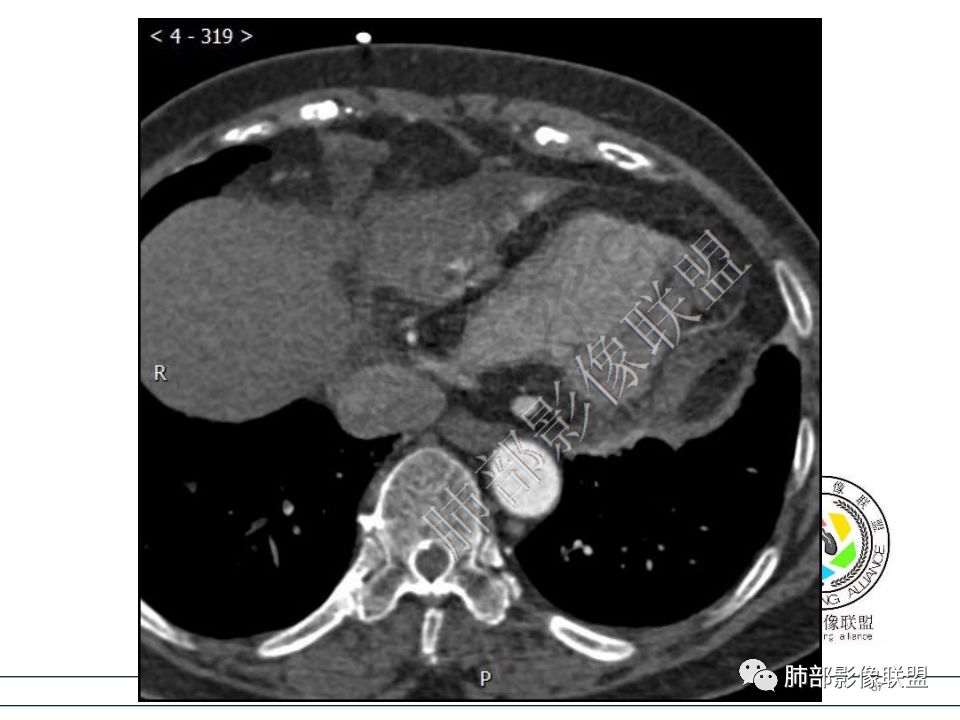

定位心包,局部与右心房分界不清,右心房受压,冠脉受压,渐进性强化,没有心包积液,考虑心包来源或右心房游离壁来源血管瘤。 医学百科网 | YxBaike.Com

从心底沿右侧房室沟一直延伸至近膈面,心包来源可以解释的通;另外病变与右心室右心房之间的脂肪间隙一直存在。

对的,心包太硬,很难突破。这例压迫右房、三尖瓣环。

熊桅: 医学百科网 | YxBaike.Com

冠状静脉窦增粗,下腔粗,回心血流受限,影响右心舒张,相当于右心衰。 医学百科网 | YxBaike.Com

心包海绵状血管瘤 医学百科网 | YxBaike.Com